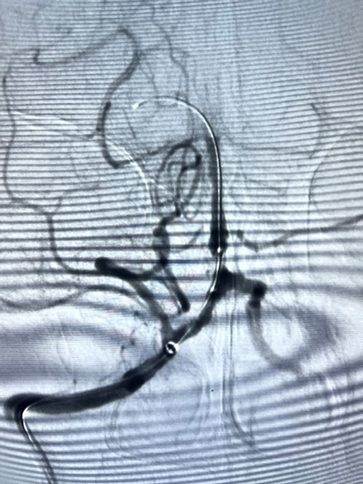

通过微导丝将赛诺神畅 Neuro LPS™2.0*10mm送入狭窄部位。

球囊通过病变